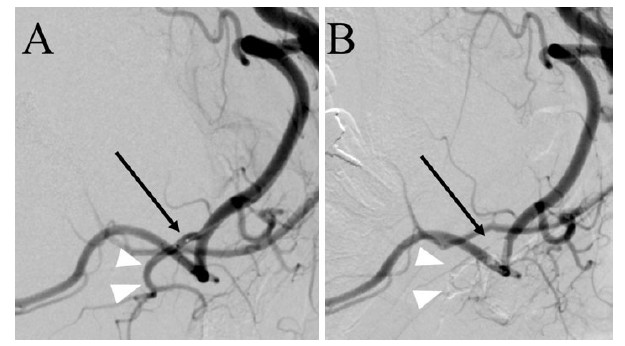

This raised concerns about the potential for mandibular fractures in the future. To prevent the progression of bone deficit, it was considered to block the pulsative pressure from a submental artery. For that reason, the submental artery occlusion by the endovascular intervention was performed. Using right femoral artery approach, a microcatheter (Defrictor Nano: Medico’s Hirata, Osaka, Japan) was guided from the left external carotid artery to the facial artery and submental artery. Endovascular occlusion glue of n-butyl-2-cyanoacrylate (NBCA) was injected from a microcatheter at a concentration of 33%. Disappearance of blood flow in the submental artery was confirmed (Figure 3).

Figure 3: Endovascular intervention angiography: (A) shows a lateral side view of the left external artery angiography prior to embolization. (B) shows the left external carotid artery angiography after embolization. The black arrows indicate the position of the microcatheter tip in the proximal submental artery. White arrowheads indicate the submental artery. In the post-embolization phase, the flow of the submental artery disappears (arrowhead portion in B).

The submental artery branches off from the facial artery and supplies blood to the chin region from the inner side of the mandible. Occlusion within this branch is generally not problematic, whereas occlusion of the facial artery itself may cause taste disorders or sensory disturbances in the tip of the tongue. Therefore, during endovascular embolization, it was necessary to reliably guide the microcatheter to the submental artery and occlude that vessel. The submental artery supplies blood to the mental region, along the mandibular midline. Combined with blood flow from the contralateral side, it perfuses the tissue, making the risk of major complications from unilateral embolization relatively low.